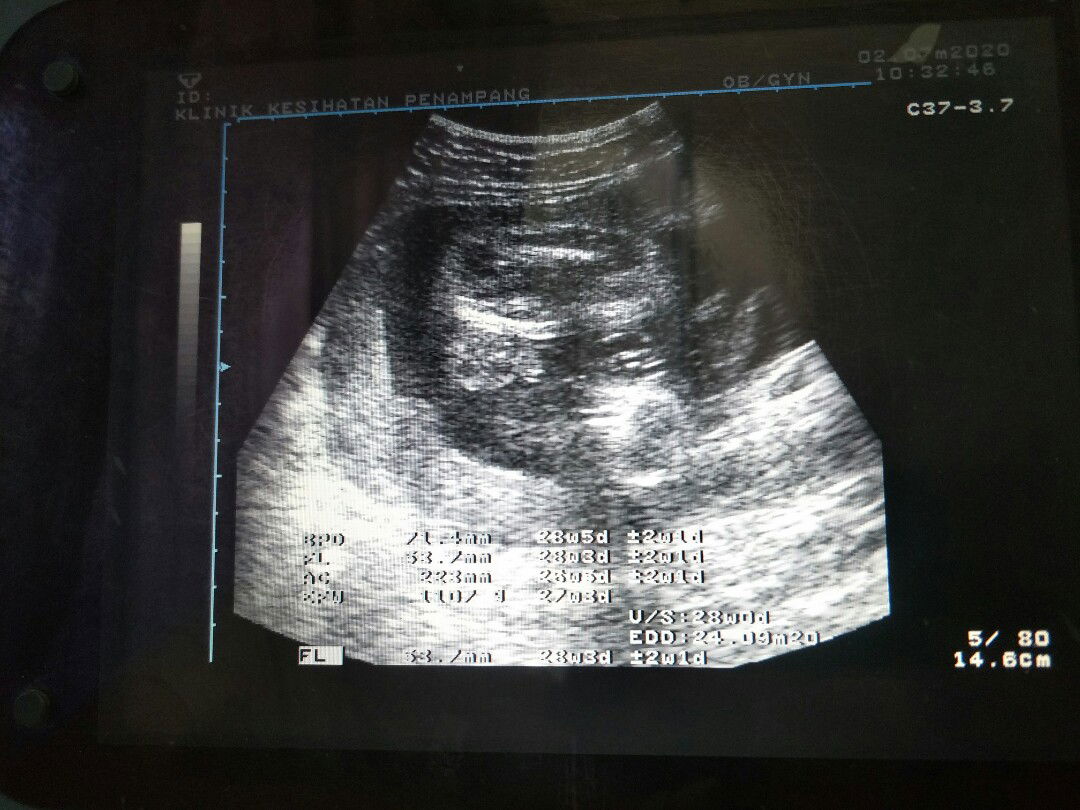

Hello, Macam mana nak kenal pasti jantina baby dalam gambar scan ni?

Dlm gmbar ni boy. Kalau nak tahu girl rupa dia mcm burger, memanjang leper. Kalau boy, ada 2 bulat. Mcm dlm ni nmpak 2 bulat.

Mcm boy, klau girl tulang/line bentuk W